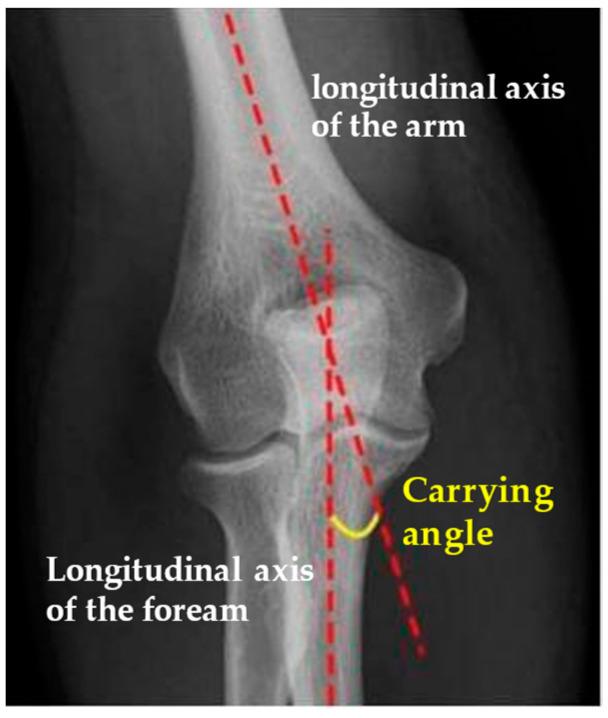

Fractures of the lateral condyle of the humerus are one of the most common fractures in children, accounting for between 10% and 20% of fractures involving the elbow, with a peak incidence at 6 years of age. Treatment is often surgical for displaced fractures > 2 mm, according to Milch and Jakob classification. There is no consensus in the literature about the appropriate surgical management of these fractures. : The aim of this study is to describe, propose, and evaluate outcomes and complications of the surgical technique of reduction and osteosynthesis using trans-bone suture with resorbable threads. : Patients with lateral condyle fractures treated with this surgical technique from 2015 to 2019 were included in this retrospective study, with a minimum follow-up of 24 months. For clinical and functional assessment of the elbow, Mayo Elbow Scores were recorded; we assessed the time of fracture healing, carrying angles, and Baumann angle of the affected limb compared to the healthy contralateral elbow for radiographic data. Complications have also been described. : We achieved satisfactory results; 36 patients with lateral condyle fractures were included in this study. Radiological healing was achieved in all cases. There was only one complication. No cases required additional surgical procedures. Almost all patients achieved a complete flexion of 110 degrees or more and complete extension. : This surgical technique has good functional outcomes and fracture healing, a lower incidence of complications when compared to other surgical techniques, and no mechanical failure with good clinical and radiological results.

肱骨外侧髁骨折是儿童最常见的骨折之一,占肘部骨折的10%至20%,发病高峰年龄为6岁。根据米尔奇(Milch)和雅各布(Jakob)分类法,对于移位超过2毫米的骨折,治疗通常采用手术治疗。关于这些骨折的适当手术管理,文献中尚无共识。本研究的目的是描述、提出并评估使用可吸收线经骨缝合进行复位和骨固定手术技术的结果及并发症。本回顾性研究纳入了2015年至2019年采用该手术技术治疗的外侧髁骨折患者,最小随访时间为24个月。对于肘部的临床和功能评估,记录梅奥肘关节评分;对于影像学数据,我们评估了骨折愈合时间、携带角以及患侧肢体与健康对侧肘部相比的鲍曼角。还描述了并发症情况。我们取得了满意的结果;本研究纳入了36例外侧髁骨折患者。所有病例均实现了放射学愈合。仅出现1例并发症。无需进行额外的手术。几乎所有患者均实现了110度或更大角度的完全屈曲和完全伸展。该手术技术具有良好的功能结果和骨折愈合情况,与其他手术技术相比并发症发生率较低,且无机械故障,临床和放射学结果良好。